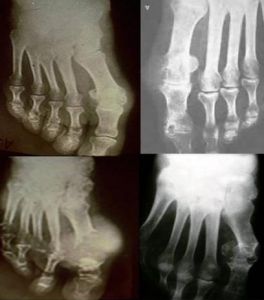

高尿酸血症6、X線檢查:

骨關節為痛風患者常見的受累部位。骨骼內還有大量鈣鹽,因而密度較高並與周圍軟組織形成良好對比。因此,病變易為X線檢查所顯示。普通X線攝片和X線數字攝影(CR或DR)簡單易行,費用較低,可顯示四肢骨關節較為明顯的骨質改變、關節間隙和骨性關節面異常及關節腫脹。

沉積在關節內的痛風石,根據其灰化程度的不同在CT掃描中表現為灰度不等的斑點狀影像。痛風石在MRI檢查的T1和T2影像中均呈低到中等密度的塊狀陰影,靜脈注射釓可增強痛風石陰影的密度。兩項檢查聯合進行可對多數關節內痛風石做出準確診斷。